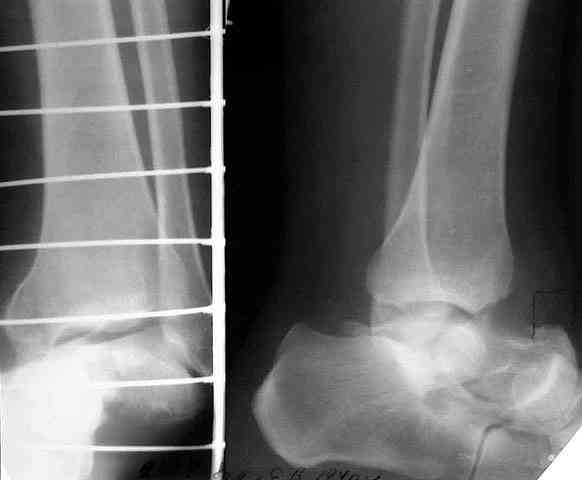

той остеотомией, которая делается для отворачивания кожно-костного лоскута с малоберцовой костью. Фиксируем все это аппаратом (пример в приложении) около 4 мес.

В итоге: мы планируем выполнить пациенту большеберцово-пяточный артродез в аппарате Илизарова с одновременной остеотомией берцовых костей и их последующим удлинением. Возможно, мы дополним фиксацию артродезируемых костей винтами.